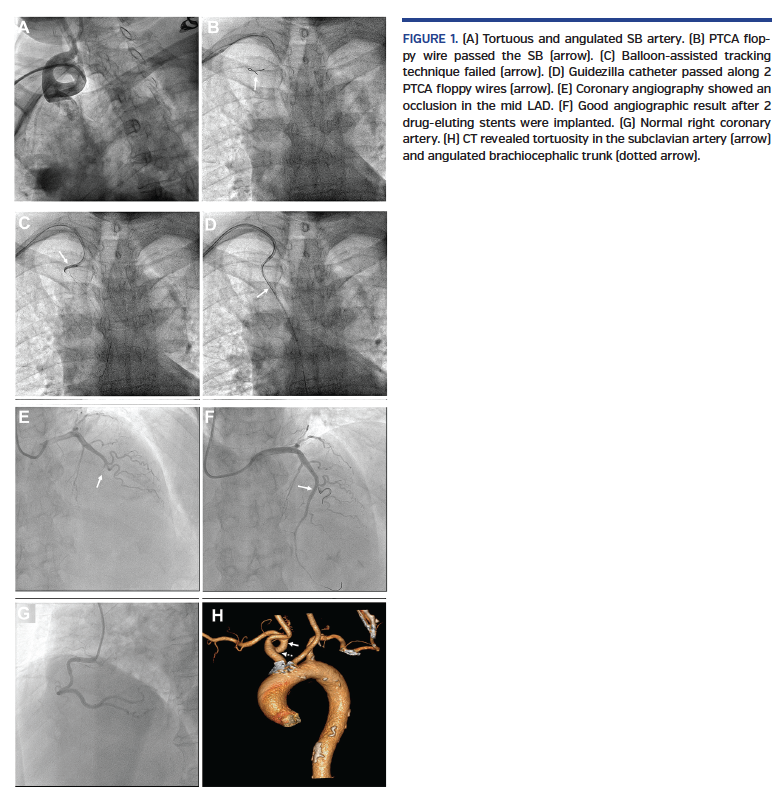

A 60-year-old woman with hypertension and type 2 diabetes mellitus presented with chest pain of 8-hour duration for anterior myocardial infarction. Immediate coronary angiography was performed via right radial artery. A 0.035˝ standard wire and 0.025˝ hydrophilic wire failed to pass the subclavian-brachiocephalic (SB) artery. Catheter angiography revealed a very tortuous and angulated SB artery (Figure 1A; Video 1), which was crossed with a 0.014˝ percutaneous transluminal coronary angioplasty (PTCA) floppy wire (Figure 1B; Video 2). However, the advancement of a 5 Fr diagnostic catheter and 6 Fr JL 3.5 guide catheter, as well as the balloon-assisted tracking technique (Figure 1C; Video 3) all failed. Finally, a 6 Fr Guidezilla catheter (Boston Scientific) easily negotiated over 2 PTCA floppy wires down to the ascending aorta (Figure 1D) and the JL 3.5 guide catheter passed over the Guidezilla to the aortic root successfully (Videos 4-6). Coronary angiography showed a total occlusion of the mid left anterior descending (LAD) artery, which was stented (Figures 1E, 1F), and a normal right coronary artery (Figure 1G). Subsequent computed tomography (CT) scan confirmed the extremely tortuous and angulated SB artery. The patient was discharged uneventfully and was asymptomatic at 1-year follow-up. This case highlights the novel use of the Guidezilla catheter to facilitate guide catheter use during transradial intervention by overcoming a tortuous and angulated SB artery.